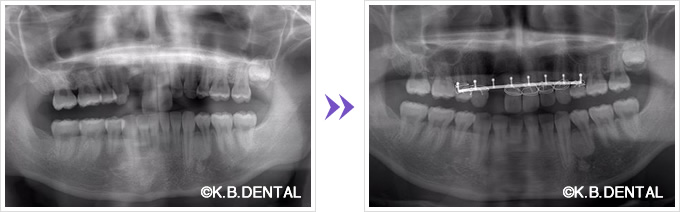

歯槽骨骨折、歯牙亜脱臼

外傷による歯槽骨骨折、歯牙亜脱臼 症例

外傷による歯槽骨骨折、歯牙亜脱臼。整復~線福子固定を行いました。できる限りの救急対応も行っております。

料金は保険適用で約10,000円の治療費用です。